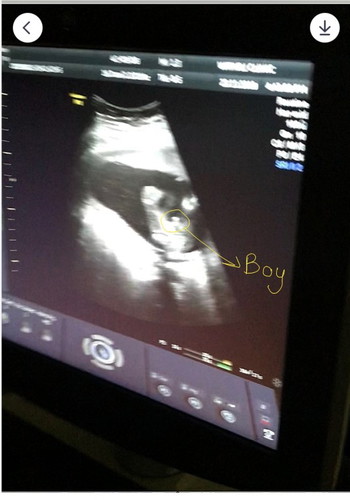

18w จู๋โผล่แล้วจ้า?

แม่ๆบ้านไหน ซาวด์แล้วได้เพศไหนกันบ้างคะ บ้านนี้อยากได้ลูกชายอยู่แล้ว ได้ลูกชายสมใจเลยคะ?

บ้านนี้เห็นชัดเจนมากค่ะตอนหมอให้ดูในใจลุ้นมากอยากได้ ผญ น้องอ้าขากว้างมากแอบเสียใจนิดๆแต่ก้อดีใจค่ะ เพราะยังใงก้อลูก